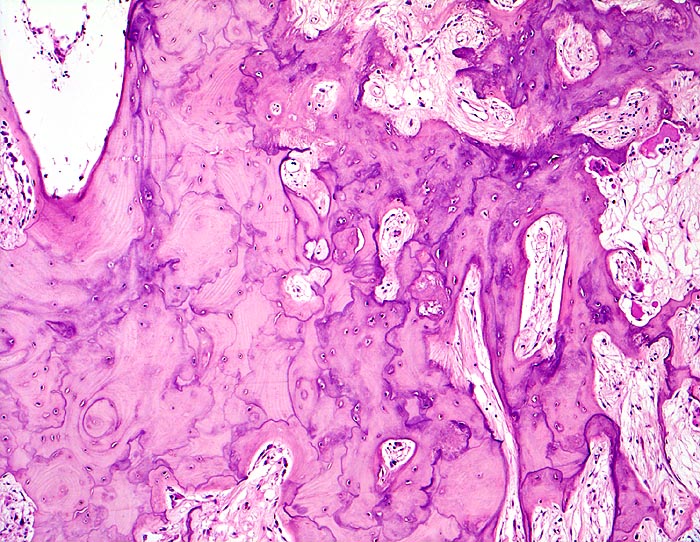

Morbus Paget des Knochens

Knochen, Tibia

Verbreiterte unregelmässig geformte Spongiosabälkchen mit mosaikartig verlaufenden Kittlinien. Markfibrose. Auffallend grosse Resorptionslakunen mit grossen Osteoklasten.

Für die histologische Diagnose eines Morbus Paget sind folgende Strukturen entscheidend:

Riesenosteoklasten mit mehr als 12 Zellkernen pro Osteoklast

grosse Resorptionslakunen

stimulierte Osteoblasten

milde Endostfibrose

girlandenartig verlaufende Kittlinien

Histologie

50